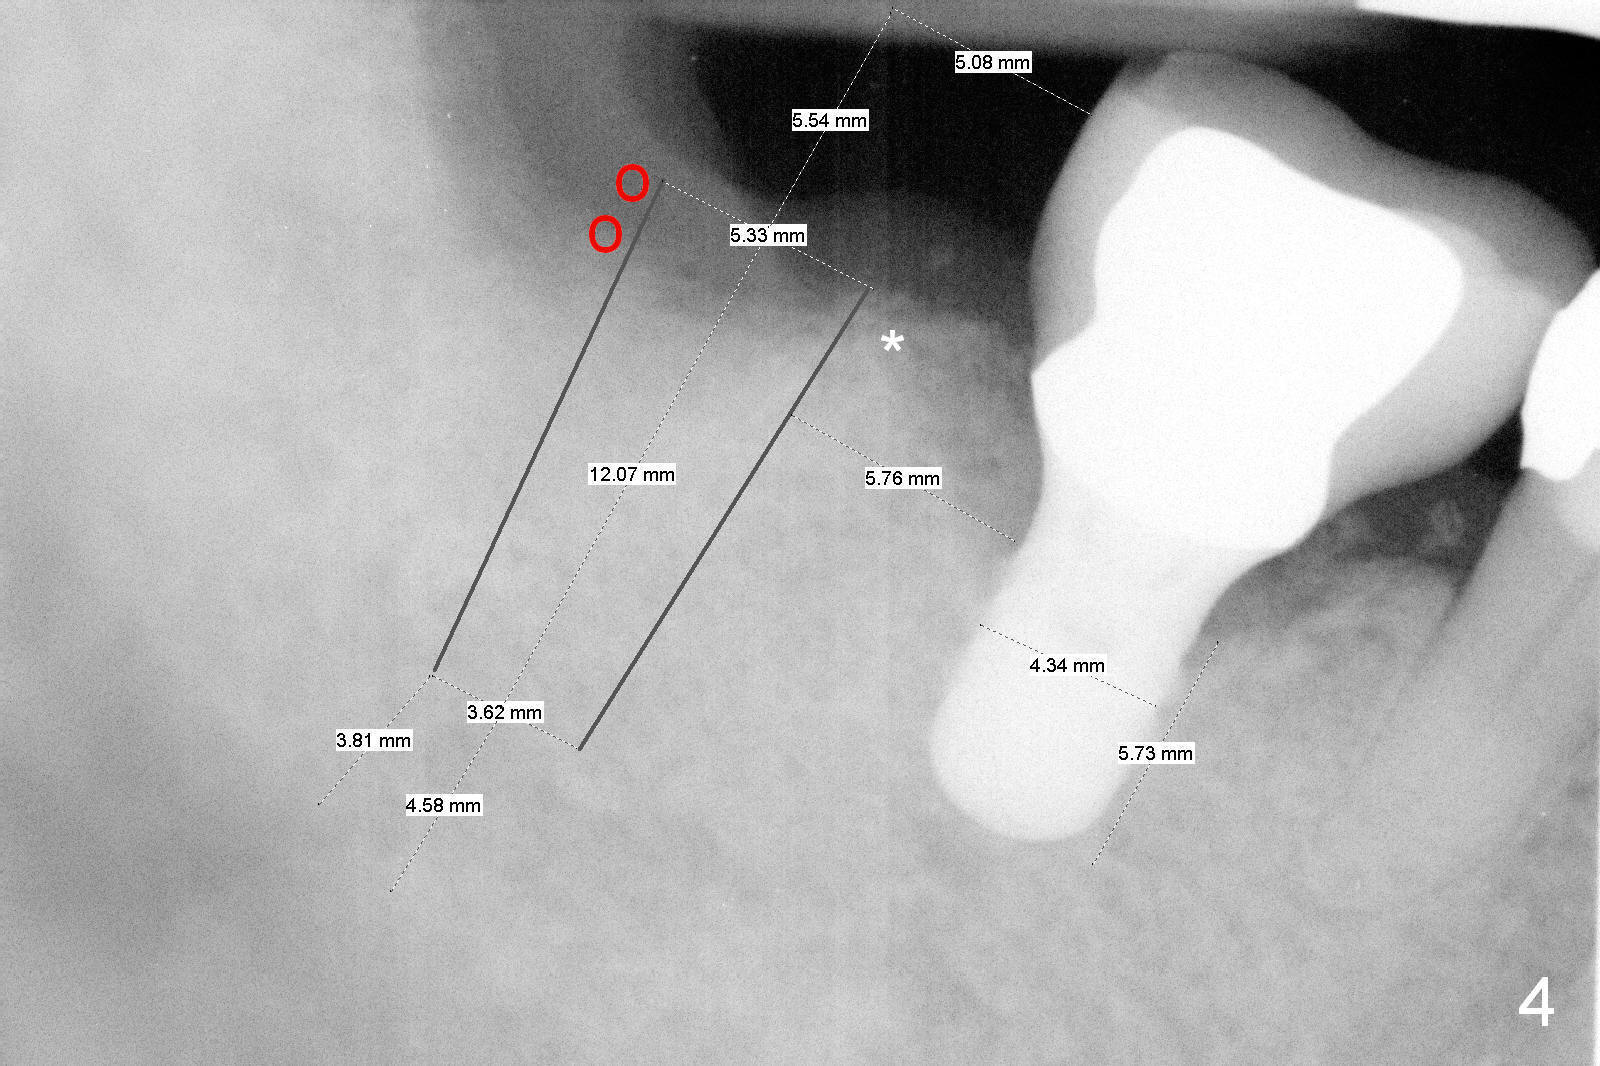

The design in Fig.4 overcomes these 2 shortcomings. The center of the implant is 5 mm from the neighboring tooth. Mesially there is more bone support (*), whereas distally bone graft is necessary (red circles). There is still enough space between the two implants; the minimum is 3 mm.

No matter which design, there is possibility of the buccal threads of the implant. Bone graft is expected. Collagen dressing should be cut in a ring shape, fixed by an abutment.